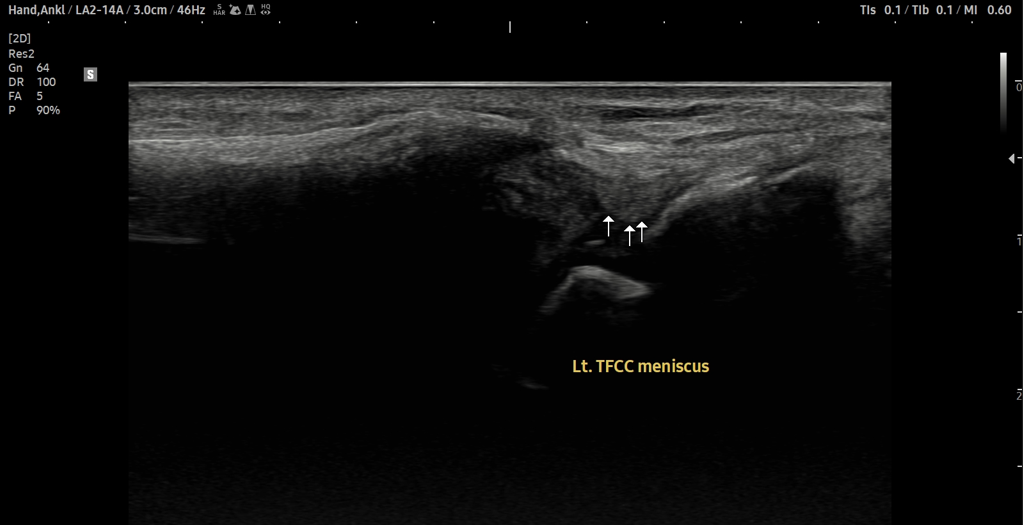

- 치료기간 : 25. 7 . 15 ~ 25. 11 . 18

- 치료횟수 : 25(5cycle) 회

[후기]

치료 전

치료 후